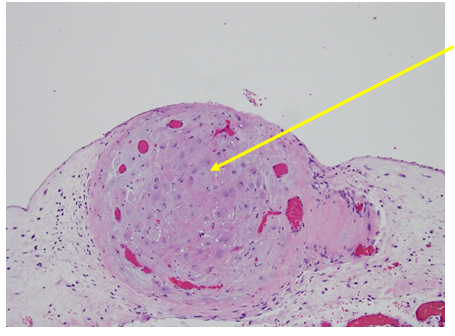

Figure 3 Higher Magnification of Box 1B from Figure 1: Stromal cells resembling decidua, Hematoxylin and Eosin Stain (H&E stain or HE stain).